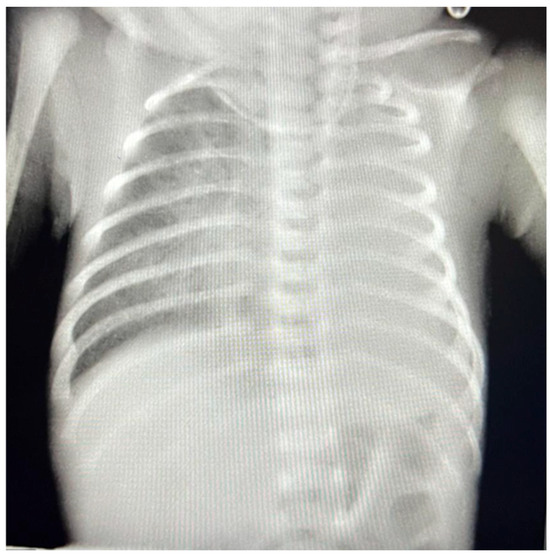

2. Case Presentation

2.2. Postoperative Management